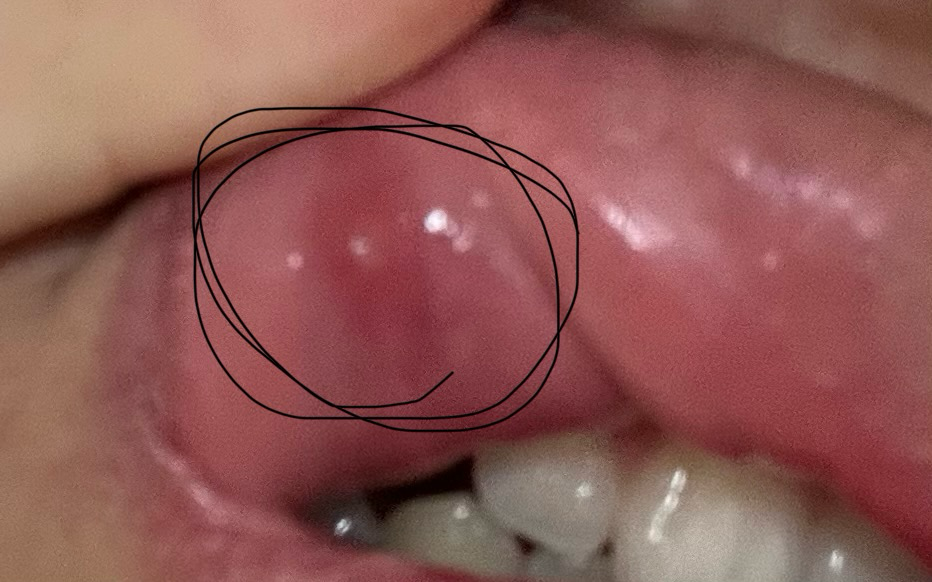

구강내 점액 낭종이 생긴 겁니다. 반복된 외상에 의해서 생기는 건데, 수술을 해서 없애줘야 됩니다.

일시적인 단순 포진일 가능성이 높아 보이며, 시간이 경과하면 스스로 좋아질 가능성이 높아 보입니다. 경과를 지켜보시되 장기간 차도가 없다면 이비인후과 등 진료 및 검사를 받아보시길 권고드립니다.